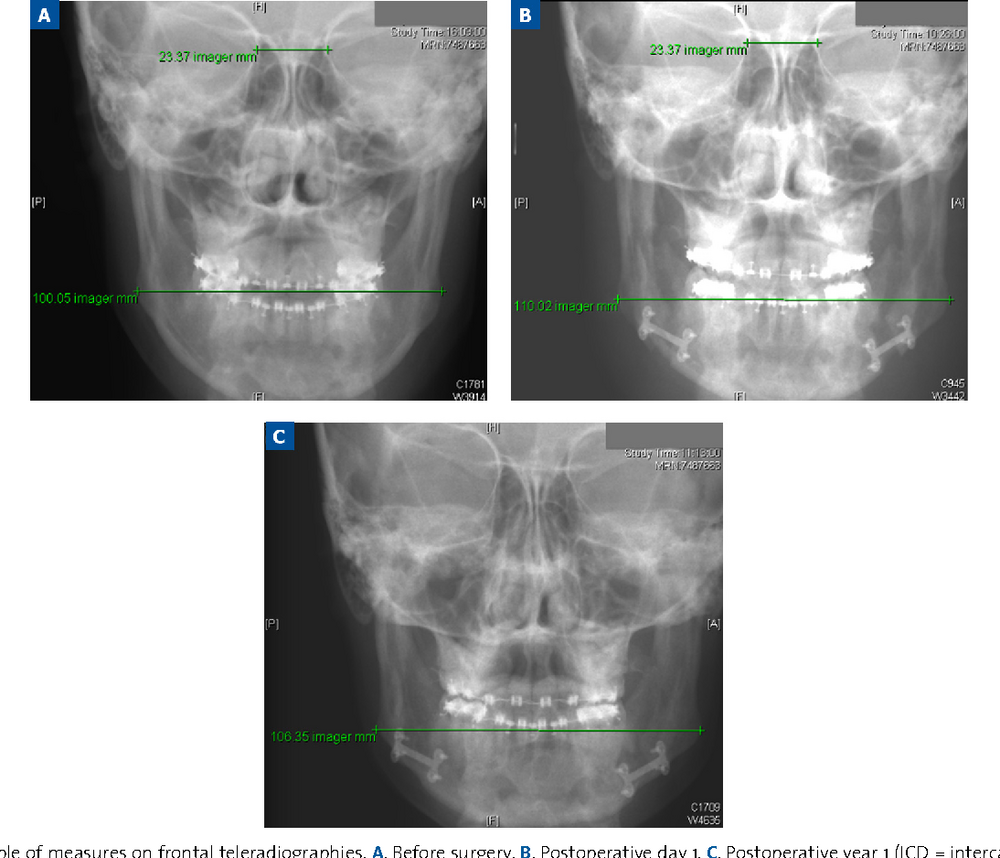

https://www.semanticscholar.org/pap...ahon/7ba8b84eeef2c292ef09a21455a049333d5559b7